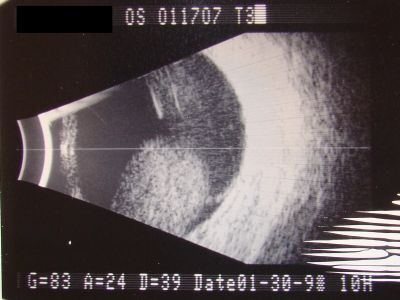

Melanoma - Large Ciliary Body B-Scan ultrasound shows tumore filling much of the eye